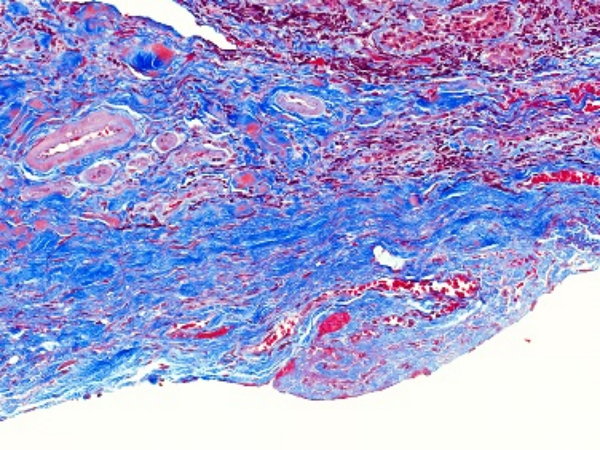

MASSON染色利用不同染料分子與組織結(jié)構(gòu)的相互作用,實現(xiàn)對膠原纖維和肌纖維的精準區(qū)分。在染色過程中,肌纖維呈現(xiàn)為紅色,而膠原纖維則呈現(xiàn)為綠色或藍色。這種色彩對比使得纖維組織在顯微鏡下變得清晰可見,醫(yī)生能夠清晰地觀察到纖維化的程度和范圍。

圖1. Masson組織染色結(jié)果示例(最右列),可看到不同處理條件下膠原纖維(藍色)和肌纖維(紅色)的分布不同

②纖維化組織染色結(jié)果

在纖維化組織中,MASSON染色會呈現(xiàn)出明顯的紅色或紫色區(qū)域。這些區(qū)域代表了膠原纖維的增生和沉積,是纖維化病變的典型表現(xiàn)。通過觀察這些區(qū)域的分布和范圍,可以初步判斷纖維化的程度和范圍。

③纖維化程度評估

根據(jù)MASSON染色結(jié)果,我們可以對纖維化程度進行初步評估。一般來說,紅色或紫色區(qū)域越多、越密集,說明纖維化程度越嚴重。同時,還可以結(jié)合其他病理特征,如纖維束的粗細、排列方向等,進行更全面的評估